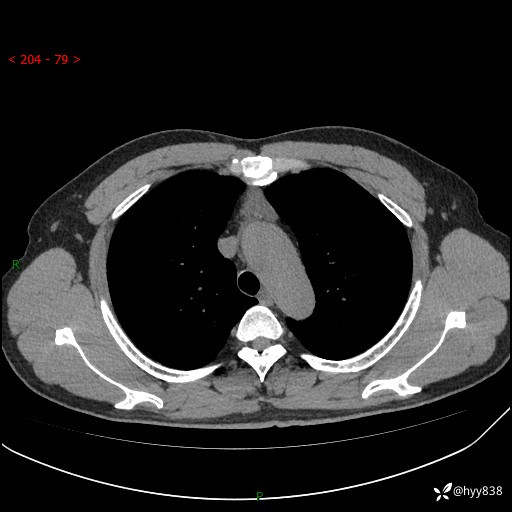

患者性别:女

患者年龄:49岁

简要病史:跟骨骨折,常规CT发现纵隔占位

胸部CT平扫